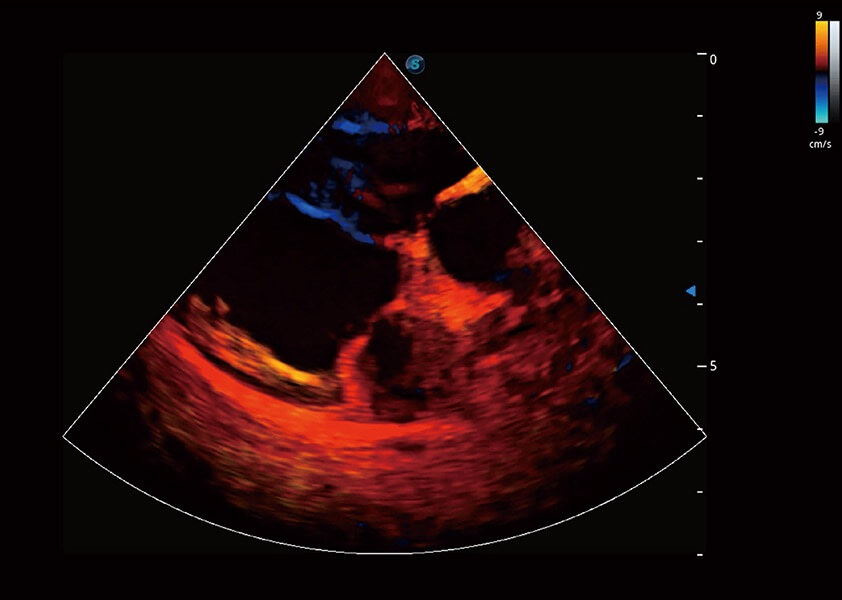

心脏解决方案

ProPet 60 配备了丰富的心脏探头群、先进的成像技术和专业的心脏测量工具,可帮助动物医生为不同体型和生理结构的动物提供心脏和心肌功能的全面评估。

• TDI 组织多普勒成像

实时用颜色表示心肌组织运动,观察和定量组织的运动情况,对快速检测与评估心肌的灌注和活性、电传导及心肌收缩和舒张功能等均能提供重要的诊断信息。

优异的基础图像

(犬)心脏组织多普勒